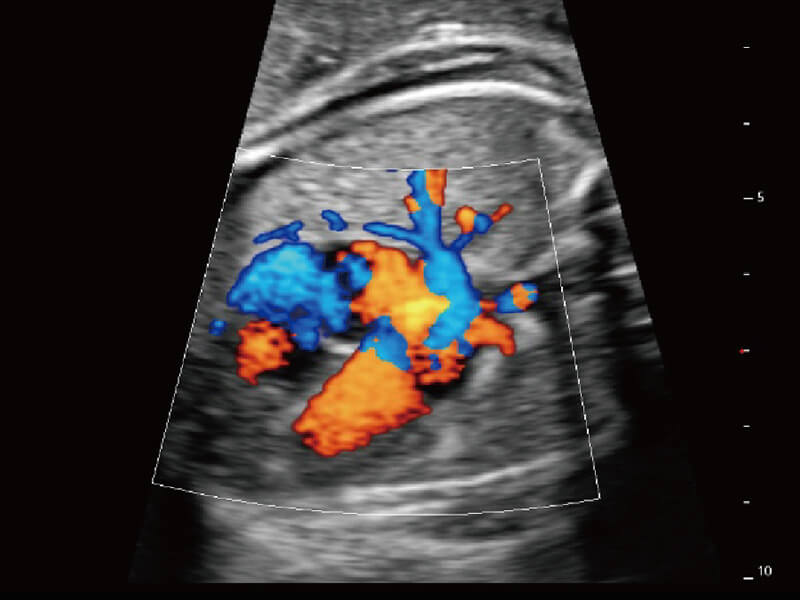

成像功能

S60探头工艺,从前端信号处理每一个环节采集无损声学数据,真实还原组织原貌,再现解剖细节。